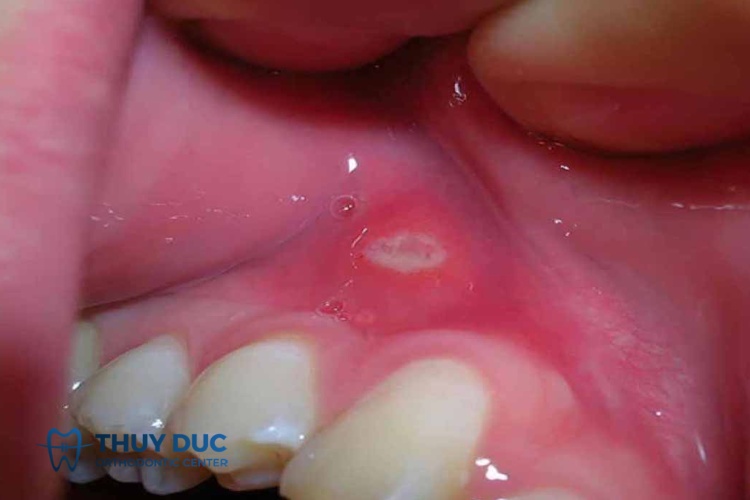

Những vết loét do nhiệt miệng có thể xuất hiện ở vị trí bất kỳ trong khoang miệng, thường gặp nhất là ở niêm mấcu môi, niêm mạc má, lưỡi, lợi, vòm miệng và thành họng. Dưới đây là một số hình ảnh nhiệt miệng để bạn đọc tham khảo:

Khi các tác nhân tấn công vào niêm mạc miệng, thành mạch máu bị giãn ra, tăng tính thấm và xuất hiện tình trạng phù nề. Ngay sau đó, các ổ loét bắt đầu phát triển:

- Vết loét thường xuất hiện đơn độc ở các vị trí khác nhau trong khoang miệng.

- Chỉ xảy ra loét ở niêm mạc trong khoang miệng mà không xuất hiện ở vị trí khác.

- Đầu tiên, tại những vị trí khô rát bắt đầu xuất hiện các đốm hình tròn hoặc hình bầu dục, hơi nhô cao lên khỏi bề mặt niêm mạc.

- Sau 8 – 16 tiếng, những đốm tròn này bị xói mòn và hình thành một lớp fibrin màu trắng xám trên bề mặt. Khi chạm tay vào có cảm giác đau nhói.

- Đáy vết loét nông, bờ vết loét là quầng đỏ hơi nhô cao tạo thành ranh giới rõ ràng so với vùng niêm mạc xung quanh.

- Xung quanh vết loét mềm mại, không có mùi khó chịu và không chảy máu.